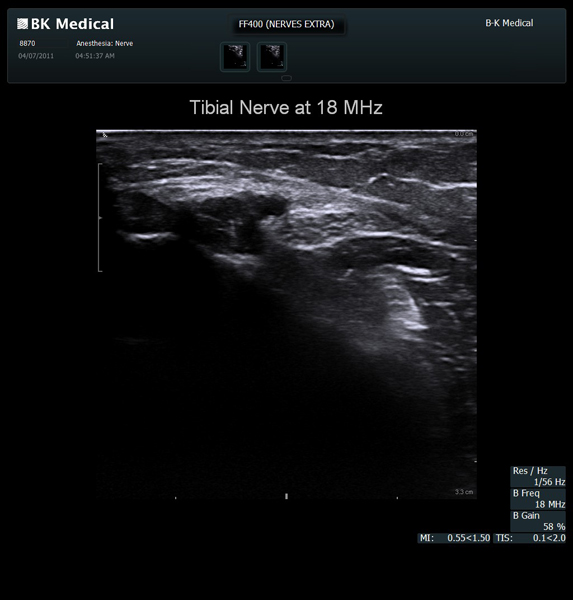

High resolution ultrasound imaging for needle-guided procedures.

The Flex Focus 400 exp ultrasound system offers premium image quality with fast frame rates for excellent temporal resolution. The system features Automatic Mode Adjustment (AMA) to optimize high resolution B-Mode Imaging when changing modes and depth.

BK Medical offers high-frequency linear transducers, imaging from 18-2 MHz for upper and lower extremities, and curved array abdominal transducer 8820e for special deep nerves or paravertebral/spinal applications. Our transducers provide superb detail that makes it easy to see your needle during procedures.